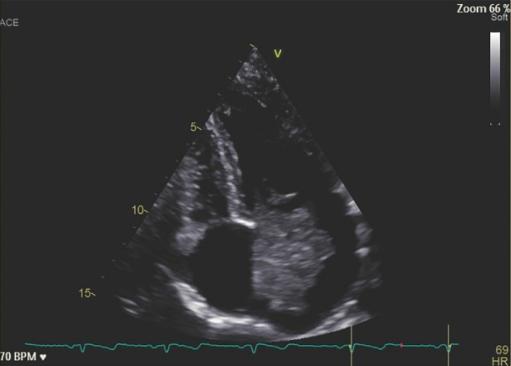

患者女性,31岁。因血清阴性起止点炎复发而入院。患者主诉双侧跖趾关节(MTP)关节痛和足底面疼痛1年,表明对抗炎药物有部分反应。关节症状发作2个月后,患者双侧足底面出现紫癜性病变(图1,左)。泼尼松50mg/d(快速减量)治疗后无改善。血液检查显示炎症指数水平升高(CRP 12 mg/dL,ESR 22 mm/h),类风湿因子(RF)和抗降钙素肽自身抗体(aCCP)阴性。肌肉骨骼超声显示双侧足底筋膜水肿(符合足底筋膜炎)和右侧掌指关节滑膜炎(MTP)(图一,右)。

图1、右脚足底侧的紫癜性病变(左)。左脚足底筋膜水肿的超声图像(横切面)(右)